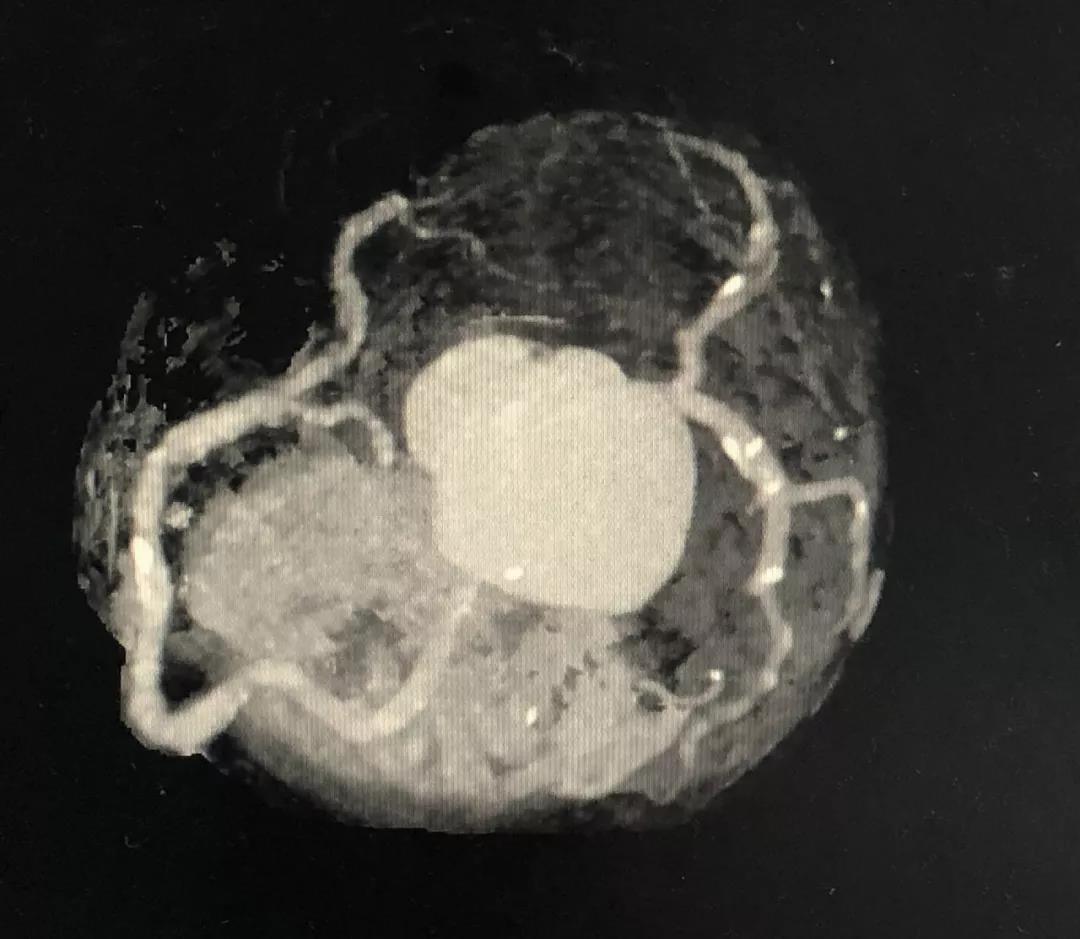

冠状动脉CTA

CCTA LAD病变特点:

近段血管较直

中远段血管偏细

中远段血管病变弥漫

病变段扭曲不很明显

病变段无重要分支发出

病变血管段有局灶点状钙化

CCTA LCX病变特点:

LM前分叉正常

LCX相对较直

中段病变伴局灶点状钙化